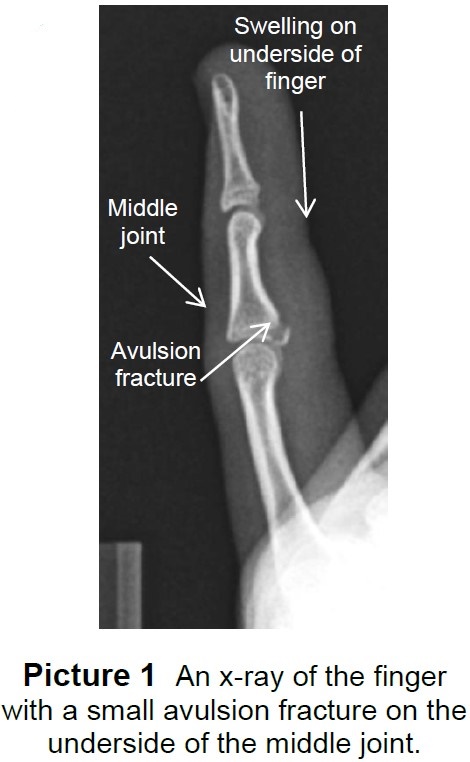

Basketball Jammed Finger Xray